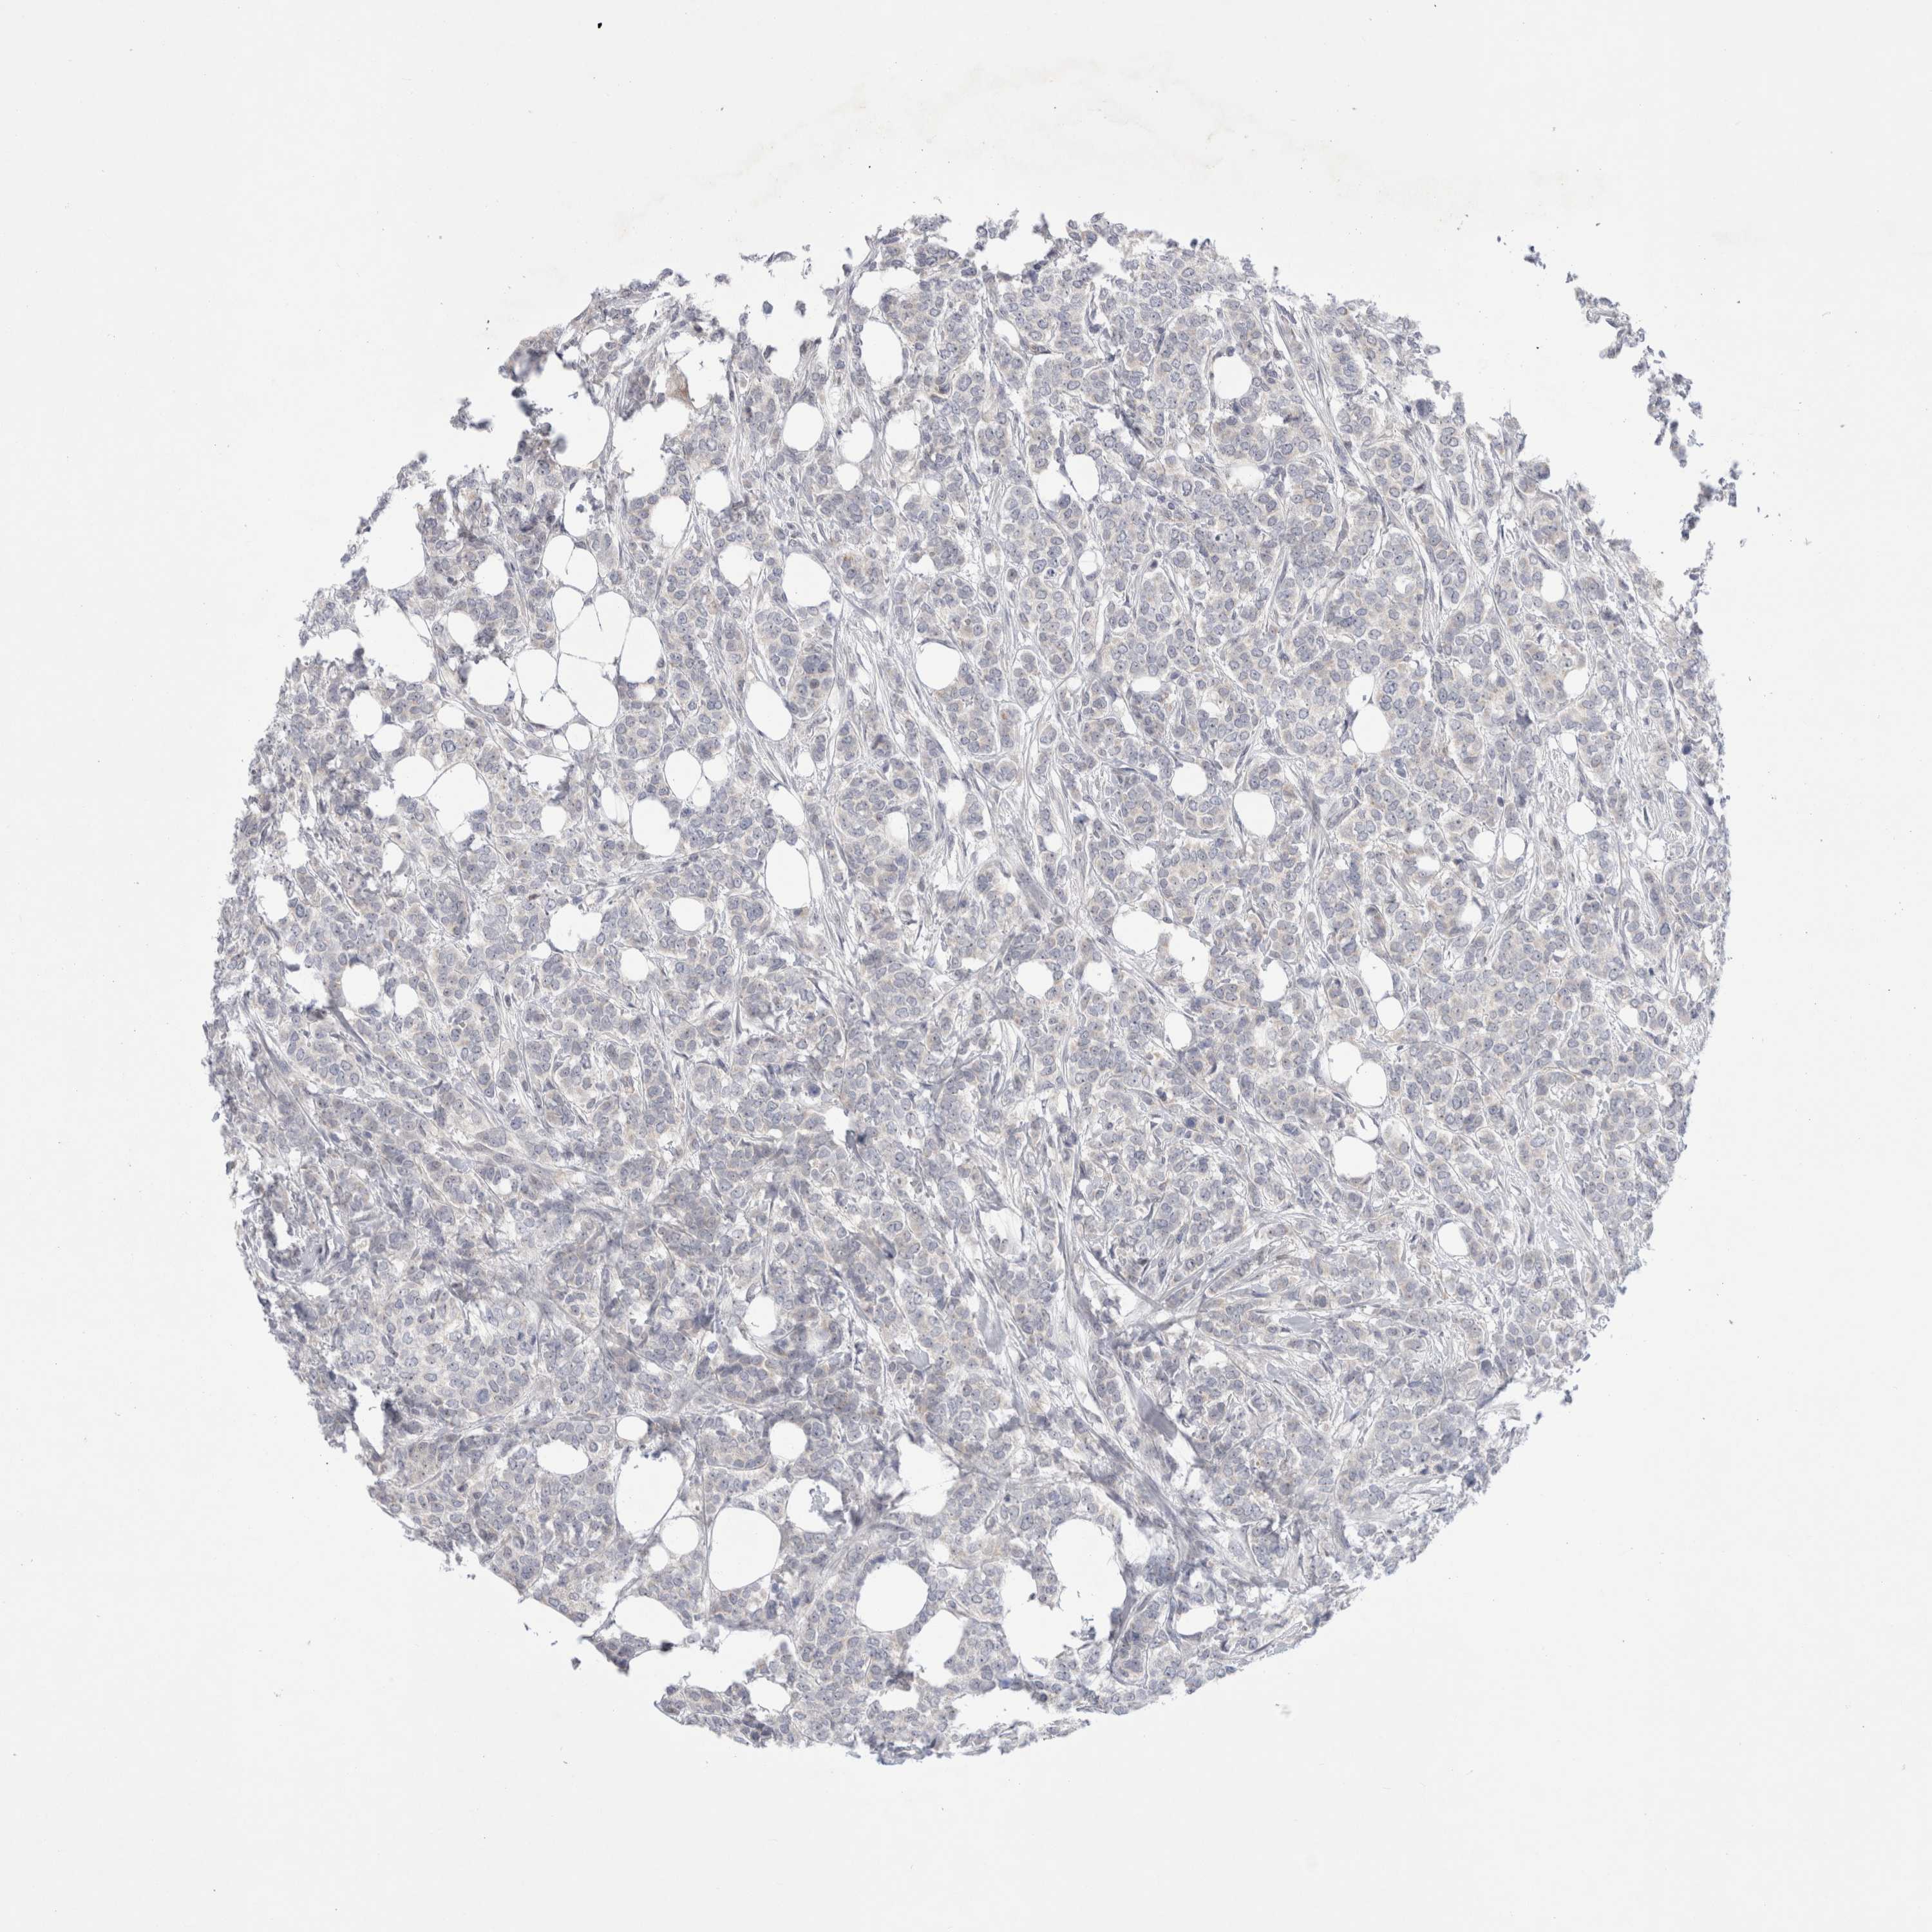

CANCER BREAST CANCER Show tissue menu

BRCA TCGA BRCA VALIDATION PROTEIN EXPRESSION

ANTIBODIES

AND

VALIDATION